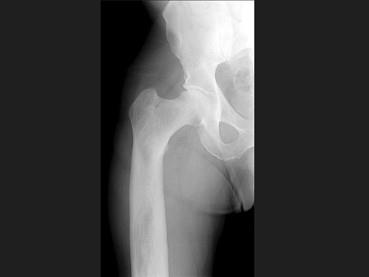

问题 男,67岁,右侧股骨痛,结合图像,最可能的诊断是?(?)

选项 A.骨纤维结构不良 B.维生素D缺乏病 C.成骨不全 D.软骨发育不全 E.畸形性骨炎

答案 E